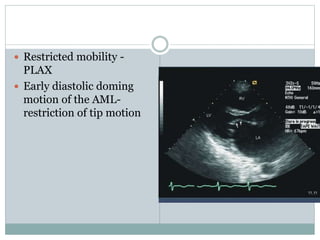

 Restricted mobility -

PLAX

 Early diastolic doming

motion of the AML-

restriction of tip motion